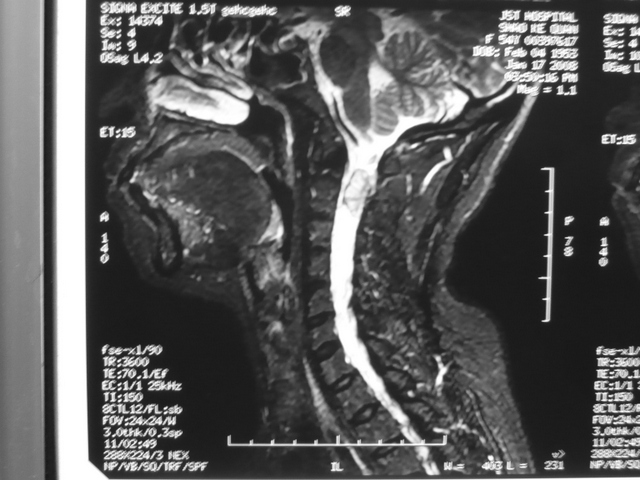

枕大孔区肿瘤

枕大孔区肿瘤枕大孔区肿瘤